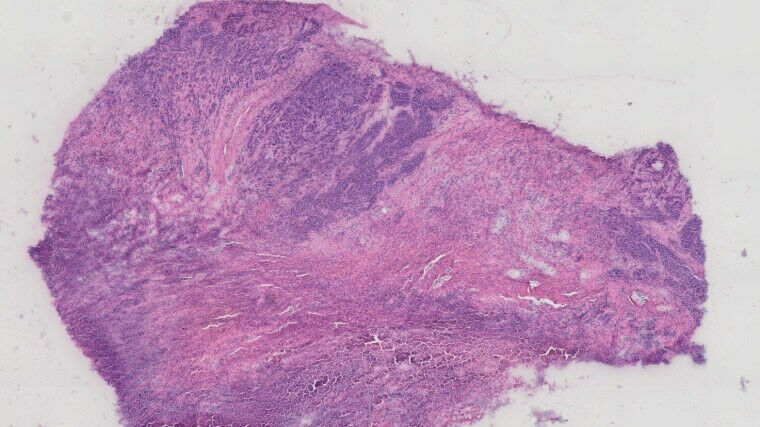

Die vollständige Entfernung eines Tumors, ohne gesundes Gewebe zu beschädigen, ist eine der größten Herausforderungen in der Krebschirurgie. Bisherige Methoden wie Gewebeentnahmen während der Operation liefern erst nachträglich Klarheit über den Behandlungserfolg. An der der Friedrich-Schiller-Universität Jena, dem Leibniz-Institut für Photonische Technologien (Leibniz-IPHT), dem Universitätsklinikum Jena (UKJ) und der Jenaer Firma Grintech hat ein Team eine Lösung entwickelt: Ein Endoskop, das mit Licht und künstlicher Intelligenz arbeitet, erkennt Tumorgrenzen präzise - ohne den Einsatz von Farbstoffen.

,,Unsere Technologie kombiniert unterschiedliche optische Bildgebungsmethoden im Rahmen eines multimodalen Ansatzes, um die chemischen und strukturellen Eigenschaften von Gewebe in Echtzeit zu analysieren", erklärt Jürgen Popp, Direktor des Instituts für Physikalische Chemie der Universität Jena und wissenschaftlicher Direktor des Leibniz-IPHT, der mit seinem Team seit über einem Jahrzehnt an der Technologie forscht. ,,Das ermöglicht es, Tumorgrenzen mit hoher Präzision zu identifizieren." Die Bildauswertung erfolgt durch Künstliche Intelligenz, die relevante Informationen blitzschnell aufbereitet und den Operierenden zur Verfügung stellt. ,,Damit können Chirurginnen und Chirurgen noch während des Eingriffs fundierte Entscheidungen treffen", ergänzt Matteo Calvarese, Erstautor

Das Besondere an der neuen Technologie: Diagnose und Therapie werden in einem Gerät vereint. Ein integrierter Femtosekundenlaser trägt krankes Gewebe präzise ab, ohne umliegendes, gesundes Gewebe zu schädigen. ,,Das Prinzip ,erkennen und behandeln’ ist ein großer Fortschritt, weil es Operationen sicherer macht und die Heilungschancen verbessert", betont Orlando Guntinas-Lichius, Direktor der Klinik für Hals-Nasen-Ohren-Heilkunde am Universitätsklinikum Jena und Mitautor der Studie. ,,Für uns als Chirurgen bedeutet das, Tumore effektiver entfernen und gleichzeitig gesundes Gewebe besser schonen zu können. Damit könnte die Zahl von Folgeoperationen und die Belastung für die Patientinnen und Patienten erheblich reduziert werden."In präklinischen Tests mit Gewebeproben von 15 Patientinnen und Patienten wurde dieses Prinzip bereits erfolgreich erprobt. Die Technologie erzielte eine Erkennungsgenauigkeit von 96 Prozent und konnte Tumorgewebe mit einer bisher unerreichten Präzision entfernen.